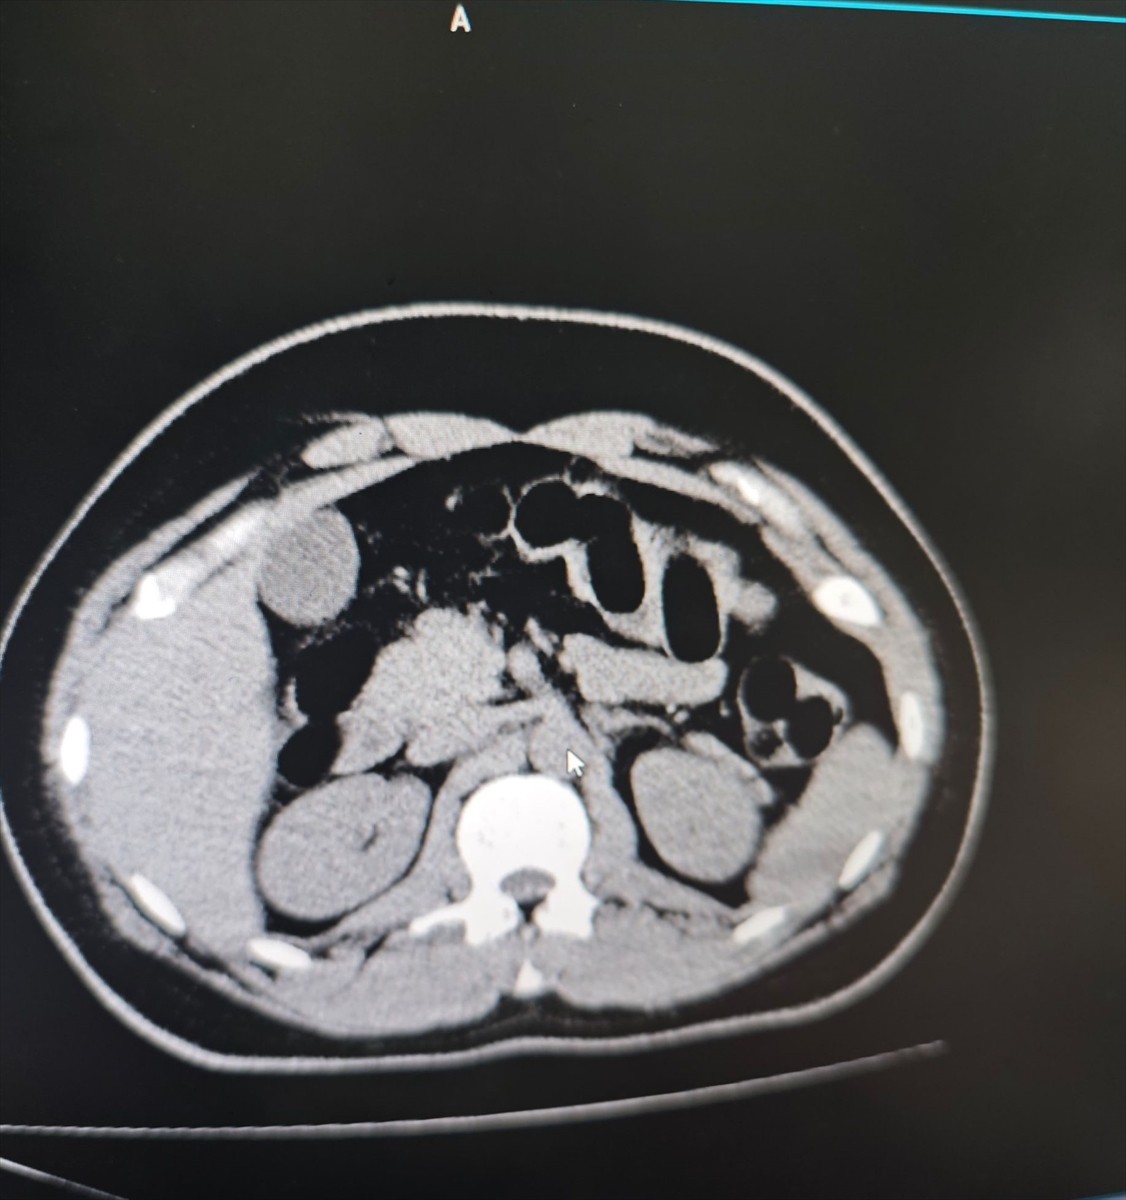

İç Bedeni Muayene Sonuçları

Hastanede yapılan iç beden muayenesi ve tomografi görüntülemesi sonucunda, şüphelinin midesinde uyuşturucu olduğu tespit edildi. Yapılan incelemeler sonucunda midesinden 84 kapsül içerisinde toplam 842 gram eroin çıkarıldı.